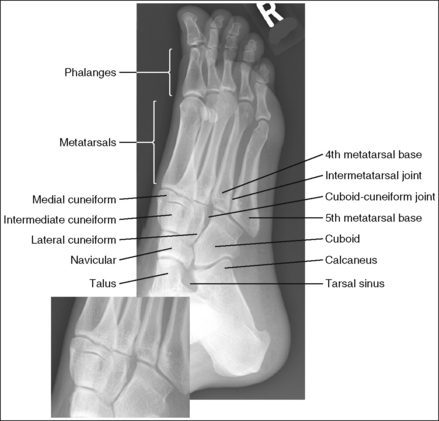

See Figure 6-12 and Box 6-5.

The foot demonstrates uniform density across the phalanges, metatarsals, and tarsals.

• When an exposure (mAs) is set that will adequately demonstrate the proximal metatarsals and tarsals, the distal metatarsals and phalanges are often overexposed because of the difference in AP foot thickness in these two regions (see Image 11). A wedge-type compensating filter placed over the phalanges and MTP joints can be used to absorb some of the photons that reach these areas, thereby obtaining more uniform foot density (Figure 6-13). Position the thinnest part of the filter 1 inch (2.5 cm) proximally to the between-toe interconnecting tissue and the thickest over the phalanges.

The foot demonstrates an AP projection. The joint space between the medial (first) and intermediate (second) cuneiforms is open, approximately 0.75 inch (2 cm) of the calcaneus is demonstrated without talar superimposition, and concavity on both sides of the first metatarsal midshaft is equal.

• An AP projection of the foot is obtained by flexing the supine patient's knee and placing the plantar foot surface against the IR (Figure 6-14). The lower leg, ankle, and foot should remain aligned, and equal pressure should be applied across the plantar surface.

• Effect of foot rotation. If the lower leg, ankle, and foot are not aligned or if more pressure is placed on the medial or lateral plantar surface, foot rotation will result, and the medial and intermediate cuneiform joint space will be closed. When the foot is laterally rotated, the navicular tuberosity, which superimposes itself on an AP projection, is rolled into profile, and the talus moves over the calcaneus, resulting in less than 0.75 inch (2 cm) of calcaneal demonstration without talar superimposition. An increase in metatarsal base superimposition also occurs (see Images 11 and 12). When the foot is medially rotated, the talus moves away from the calcaneus, resulting in more than 0.75 inch (2 cm) calcaneal visualization without talar superimposition. A decrease in superimposition of the metatarsal bases also occurs (see Image 13).

The tarsometatarsal (TMT) and navicular-cuneiform joint spaces are open.

• The bones of the foot, with their ligamentous and muscular structures, are arranged in a longitudinal arch that is visible on the medial foot surface. This arch places the tarsometatarsal and navicular-cuneiform joint spaces at a set angle with the IR. To demonstrate these joints as open spaces, angle the central ray until it is aligned parallel with them. This is accomplished in most patients by using a 10- to 15-degree proximal (toward the calcaneus) angle or aligning the central ray perpendicularly with the dorsal surface. The exact degree of angulation needed depends on the height of the longitudinal arch. A 10-degree angle should be used when the patient's longitudinal arch is low, as shown in Figure 6-15. A 15-degree angle is needed in a patient with a high arch, as shown in Figure 6-16. Higher arched patients require a slightly higher angle. Omitting or employing an inaccurate central ray angulation results in obstructed TMT and navicular-cuneiform joint spaces (see Image 14).

The third metatarsal base is at the center of the exposure field. The proximal calcaneus, talar neck, tarsals, metatarsals, phalanges, and surrounding foot soft tissue are included within the collimated field.

• To place the third metatarsal base in the center of the image, center the central ray to the midline of the foot at a level 0.5 inch (1.25 cm) distal to the fifth metatarsal tuberosity. The fifth metatarsal tuberosity can be palpated along the lateral foot surface, approximately halfway between the ball of the foot and the calcaneus.